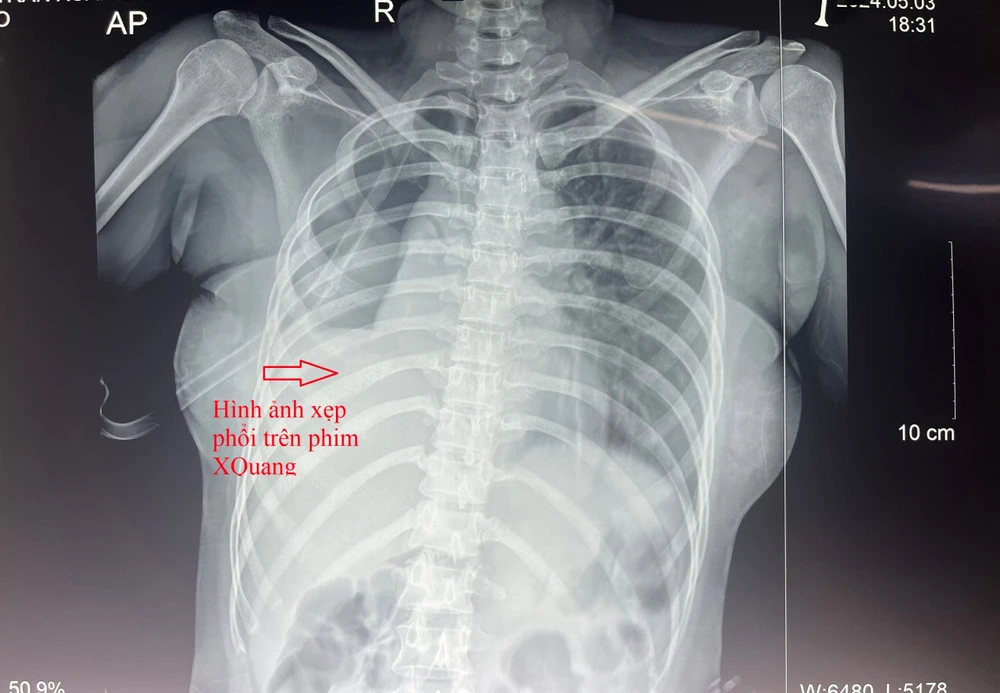

Hình ảnh xẹp phổi ,tràn khí màng phổi trên phim X quang ngực sau khi bệnh nhân bị đứt phế quản

Kết quả chụp X-quang ngực và chụp cắt lớp vi tính ngực có cản quang ghi nhận bệnh nhân bị gãy xương sườn 1-2 bên phải và 1-5 bên trái, xẹp thụ động nhu mô phổi phải, tổn thương phế nang phổi phải, tràn khí, tràn dịch màng phổi phải.